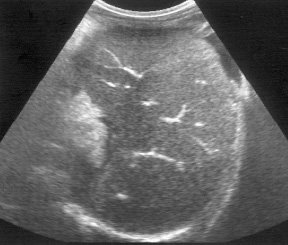

Эхографическое исследование органов брюшной полости у детей с подозрением на внепеченочнув форму портальной гипертензии практически в 100% случаев позволяет правильно предположить диагноз. Печень, как правило, нормального или уменьшенного размера. Последнее обусловлено значительным снижением портального кровотока при развитии фиброзирования паренхимы, наблюдаемом у 60-70% детей. При врожденном фиброзе от паренхимы регистрируются множественные мелкие сильные эхосигналы, рассеянные по всей площади среза органа (рис. 1). Воротная вена изменена, при этом может наблюдаться отсутствие просвета ее ствола или основных ветвей (рис. 2), наличие множественных тонких извитых сосудов с гиперэхогенными стенками, собранных вместе - ангиоматозная трансформация (рис. 3), наличие тромба, сужающего или закрывающего просвет сосуда, или локальное сужение просвета, что приводит к развитию коллатералей, видимых как анэхогенные узкие, извитые тубулярные структуры, идущие рядом с основным стволом (рис. 4). Такие изменения воротной вены приводят к значительному замедлению кровотока. Цветное допплеровское картирование облегчает качественную оценку состояния воротной вены, позволяя определить направление кровотока (гепатопетальный - к печени или гепатофугальный - от печени).

Рис. 1. Эхограмма печени при врожденном фиброзе.